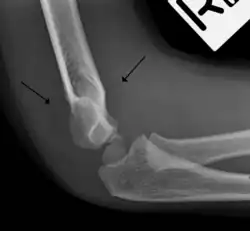

In addition to fracture, any process resulting in an elbow joint effusion may also demonstrate an abnormal fat pad sign. Increased intracapsular fluid is also seen in several conditions other than fracture and this produces the abnormal fat pad sign. (toxic synovitis, septic arthritis, Juvenile Rheumatoid Arthritis, osteomyelitis of the distal humeral physis and secondary septic joint). In these instances, history and clinical examination in addition laboratory results (WBC, ESR, CRP) will guide the provider in determining whether to treat the condition as an occult fracture or continue workup for other pathology.

The fat pad sign is invaluable in assessing for the presence of an intra-articular fracture of the elbow. An anterior fat pad is often normal. However a posterior fat pad seen on a lateral x-ray of the elbow is always abnormal. The patient will be unable to flex their elbow and requires orthopaedic input.[2]

The posterior fat pad is normally pressed in the olecranon fossa by the triceps tendon, and hence invisible on lateral radiograph of the elbow.[3] When there is a fracture of the distal humerus, or other pathology involving the elbow joint, inflammation develops around the synovial membrane forcing the fat pad out of its normal physiologic resting place. This is visible as the "posterior fat pad sign" and is often the only visible marker of a fracture, particularly in the pediatrics population.